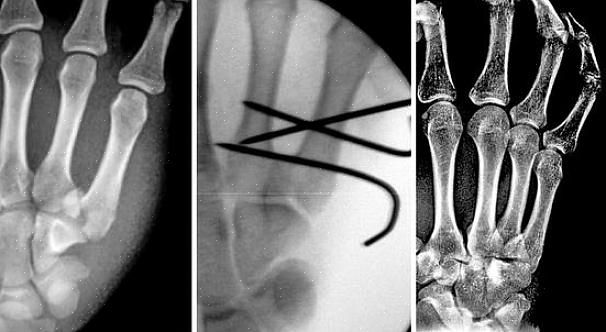

זה ייקח כשישה שבועות לעצם להחלים, אם כי זה יכול להיות ארוך יותר אם השבר חמור יותר. במקרים חמורים מאוד, ייתכן אפילו שתזדקק לניתוח.

מלכתחילה, ייתכן שתצטרך ללבוש סד כדי לשמור את האצבעות במקומן. כמה זמן אתה צריך לחכות לפני שאתה יכול להתחיל להפעיל את האצבעות שלך יהיה תלוי עד כמה חמור השבר. לאחר זמן מה, תוכל להסיר את הסד כדי להזיז יותר את האצבעות.